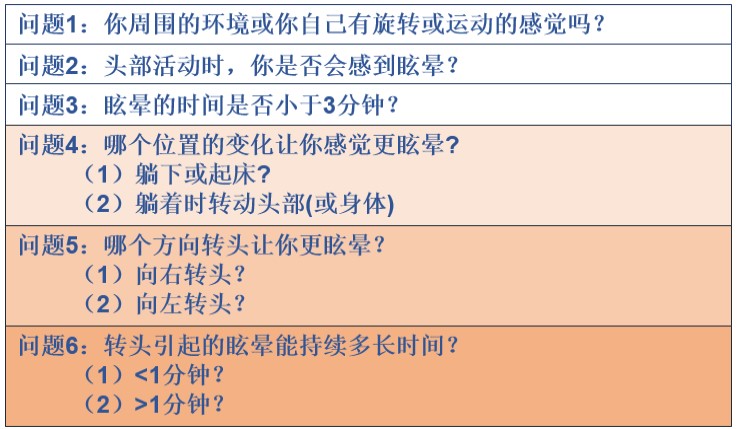

6问法简单筛查耳石症!

若前3个问题回答均为“是”,考虑为耳石症。若前3个问题中的任何一个回答为“否”,耳石症可能性不大,不必再回答剩下的问题。问题4用于区分水平半规管、后半规管耳石症。问题5用以确定哪一侧受累,问题6确定亚型。